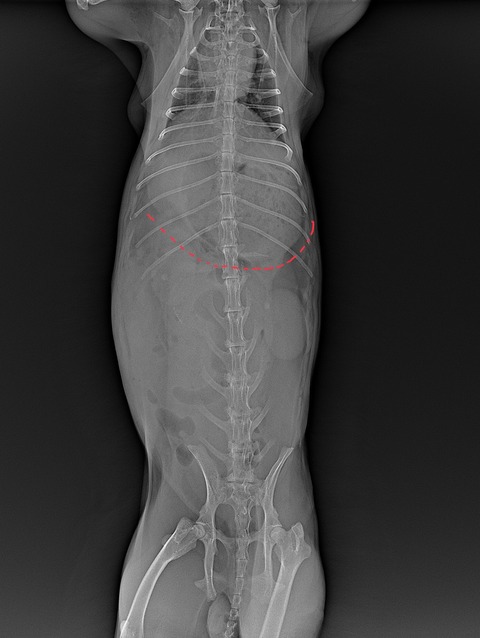

そうしてお腹の中の状態をある程度予想した上でレントゲン検査に進みます

胃腸の内容物やガスの貯留具合は実際どうか、鬱滞を起こす原因となるようなものはないか(尿路結石や腹腔内腫瘍など)といったことを評価します

⇩正常なレントゲン像

⇩異常な量の消化管ガス貯留が見られた症例